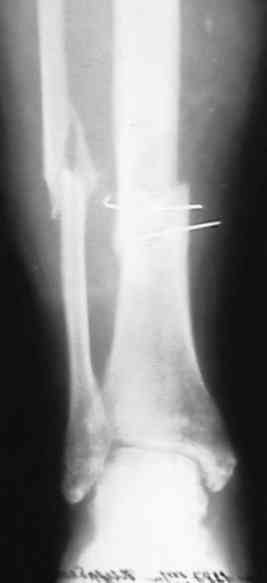

Несращение голени

поступил больной с замедленной консолидацией перелома голени . Травма ДТП 15 мая 2007года (6 мес. Назад) . Первичный диагноз : открытый перелом голени 2 А степени (Каплан-Маркова) . В одной из районных больниц выполнена трансфиксация , я так понимаю , по Паппу спицами и наложена гипсовая повязка . .Затем больной находился под наблюдением травматолога поликлиники , Свищей , длительно незаживающих ран , вроде (со слов больного) не было . ВТЭК, 2 группа . Но больной хочет ходить , (вроде нормальное желание ) На сегодняшний день имеем вот такую картинку (см. . Снимки) Анализы абсолютно нормальные . Температура 36,6 в течении суток . Клинически : отёк голени , движения в КС и голеностопном суставе практически в полном объёме . В зоне перелома определяется безболезненная подвижность , опора на конечность невозможна . PLS !!!подскажите , тактику лечения! Мой план : АВФ (БИОС недоступен) . Предполагаемый план операции: Проксимально стержень , дистально спица во фронтальной плоскости с учётом смещения . Парафрактурно оставляю <пустые> кольца . Открываю зону перелома и удаляю спицы . Остеотомия малоберцевой кости . Дистракция . В ране иссекаю межотломковую рубцовую ткань . Вскрываю костномозговые каналы . Восстановление длины и оси . Если получится ,то одномоментно . Если не нарвусь на гнойный очаг в области перелома , выполняю декортикацию . Возможно с применением аутотрансплантанта из крыла. Провожу репонирующие спицы ,стабилизирую АВФ . При наличии гнойного очага - то же самое + дебридмент , но без костной пластики и декортикации . Затем ,при благоприятном течении раневого процесса , ранняя нагрузка . При наличии проблем - ограничение нагрузки до санации раны , <аккордеонная техника> (по Голяховскому) . Прошу , выскажите замечания по технике и тактике лечения . С уважением Д.Б.